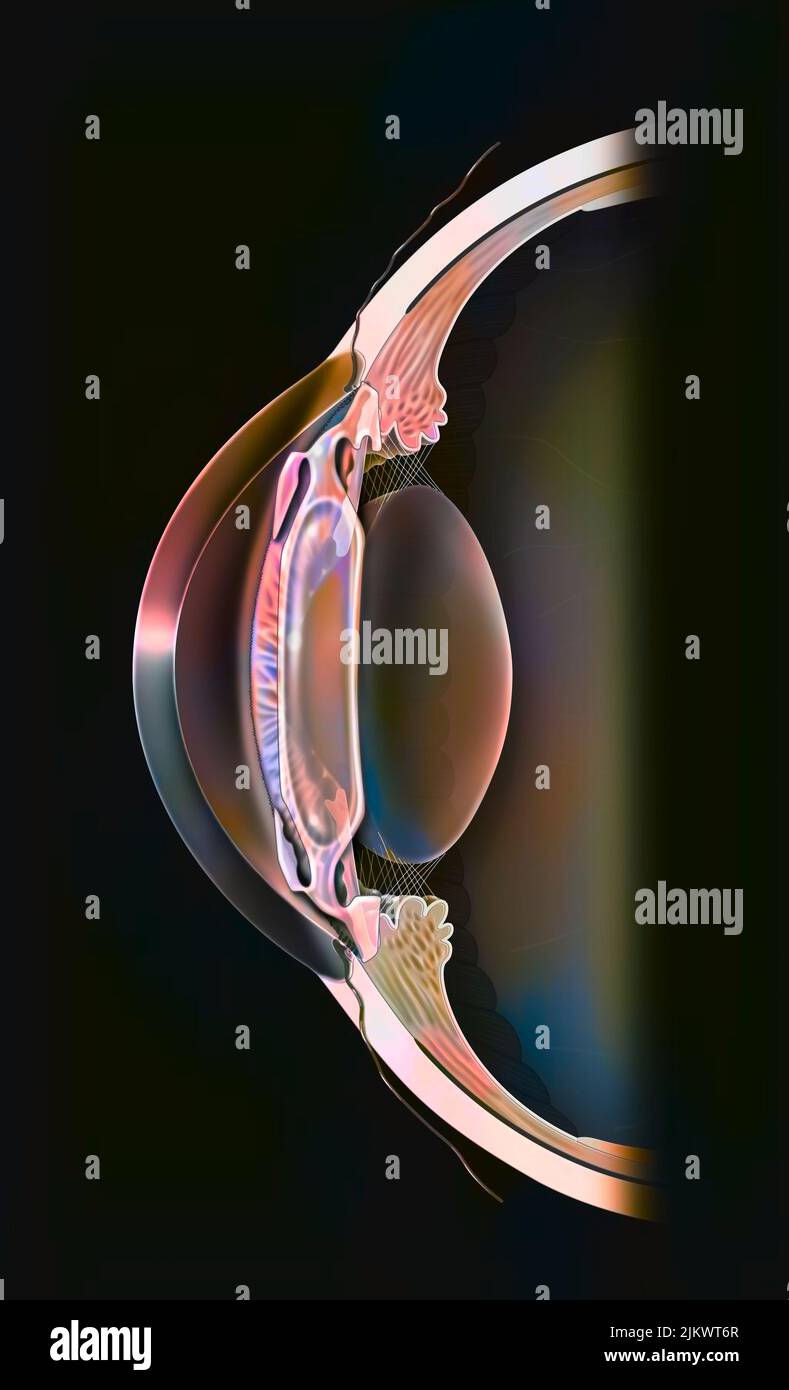

RF2JKWT9A–Oeil, cataracte, phacoémulsification - étape 2: Consiste à casser la lentille avec une sonde.